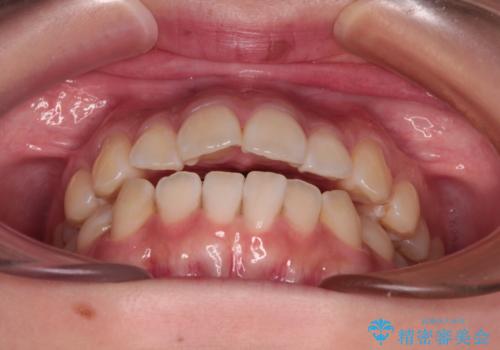

- 口元の突出感と上下前歯のズレを気にして来院された患者様です。

舌の突出癖により上下の前歯は非接触となっている状態でした。

舌のトレーニングを行わないと上下前歯の接触達成は困難であるため、トレーニングをしっかりと行っていただきながら、治療を進めて行くこととしました。

上下左右の第一小臼歯4本を抜歯し、ワイヤー装置にて矯正治療を行うこととしました。